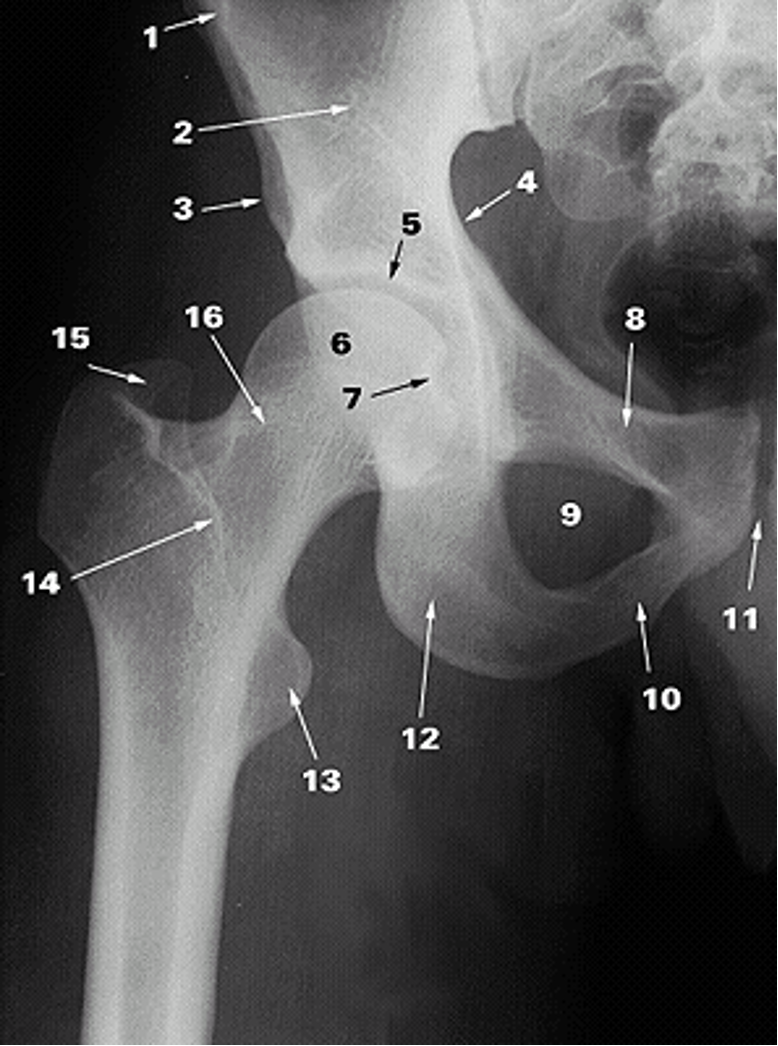

<p>1.</p>

1.

Anterior Superior Iliac Spine (2)

New cards

<p>2.</p>

2.

Ilium (2)

25

<p>3.</p>

3.

Anterior Inferior Iliac Spine (2)

26

<p>4.</p>

4.

Pelvic Brim

27

<p>5.</p>

5.

Acetabular Fossa (2)

28

<p>6.</p>

6.

Head of Femur (2)

29

<p>7.</p>

7.

Fovea

30

<p>8.</p>

8.

Superior Ramus of Pubis (2)

31

<p>9.</p>

9.

Obturator Foramen (2)

32

<p>10.</p>

10.

Inferior Ramus of Pubis (2)

33

<p>11.</p>

11.

Pubic Symphysis (2)

34

<p>12.</p>

12.

Ischium

35

<p>13.</p>

13.

Lesser Trochanter (2)

36

<p>14.</p>

14.

Intertrochanteric Crest (2)

37

<p>15.</p>

15.

Greater Trochanter (2)

38

<p>16.</p>

16.

Neck of Femur (2)